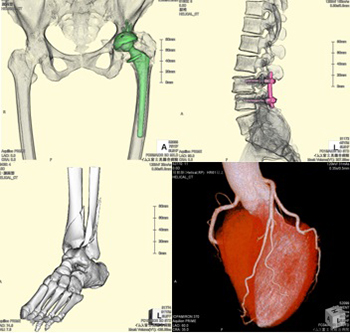

CT

- Canon Aquilion PRIME 80列

頭部から足先まで、全身の輪切りの撮影を短時間で行えます。

また造影剤を使用することにより、全身血管、心臓の撮影も行うことができます。

撮影したデータをコンピューターで処理する事で、多方向からの断面像や3D画像を作成する事ができます。